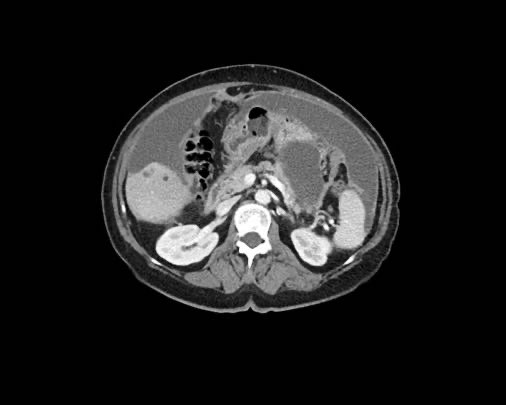

Ca lâm sàng 2

Cuộn qua các lát cắt.

Bạn có thể phát hiện tất cả các tổn thương cấy ghép phúc mạc không?